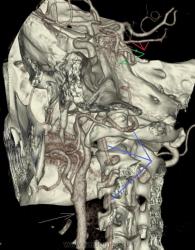

Персистирующая примитивная тройничная артерия.

Мужчина 63 лет с жалобами на опущение верхнего века справа. Направлен на КТ-ангиографию для исключения аневризмы в области сифона правой внутренней сонной артерии.

При КТА отмечается гипоплазия вертебральных артерий, больше выраженная справа. Основная артерия на большем протяжении не развита, дистальная часть ее питается из расширенной примитивной тройничной артерии, отходящей от проксимальных отделов сифона правой внутренней сонной артерии. Кроме этого правая задняя мозговая артерия отходит от супраклиноидного отдела внутренней сонной артерии – задняя трифуркация. Слева отсутствует задняя соединительная артерия.

Таким образом кровоснабжение вертебро-базиллярного бассейна осуществляется из правой внутренней сонной артерии.

Голубые стрелки – вертебральные артерии.

Красные – задние мозговые.

Зеленые – тройничная артерия.

Желтые – основная артерия.

Черные – сифон внутренней сонной.